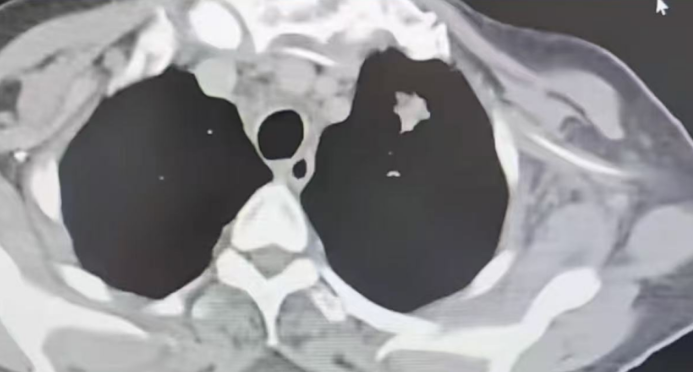

令人欣慰的是,经过两次规范治疗,患者症状明显改善:由卧床不起转为可下地自由活动,胸闷、咳嗽等症状基本消失,生活恢复自理能力,并可从事适当家务。影像学复查显示,患者双肺结节显著减少,纵隔淋巴结明显缩小,右肺门肿块也较前减小,疗效评估达到完全缓解(CR)的临床标准。